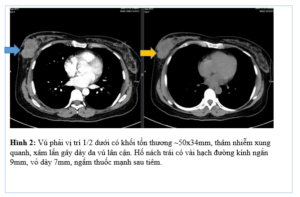

CASE LÂM SÀNG ĐIỀU TRỊ UNG THƯ PHỔI KHÔNG TẾ BÀO NHỎ ÂM TÍNH VỚI PD-L1 GS.TS Mai Trọng Khoa 1,2, PGS.TS Phạm Cẩm Phương 1,2, TS.BS Phạm Văn Thái1 BSNT. Phùng Thế Thông2 1Trung Tâm Y học hạt nhân và Ung bướu, Bệnh viện Bạch Mai 2Trường Đại học...